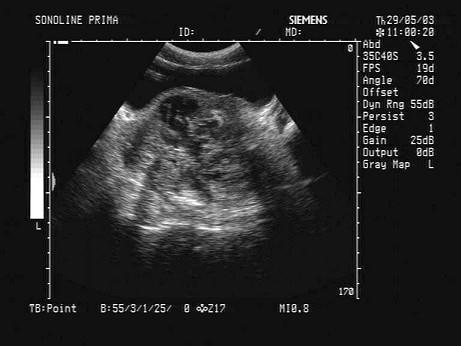

问题 某患者因血尿就诊,前列腺超声声像图如下,生化检查PSA增高,最可能的诊断为?(?)

选项 A.前列腺脓肿 B.前列腺炎 C.前列腺良性增生 D.前列腺癌 E.前列腺囊肿

答案 D